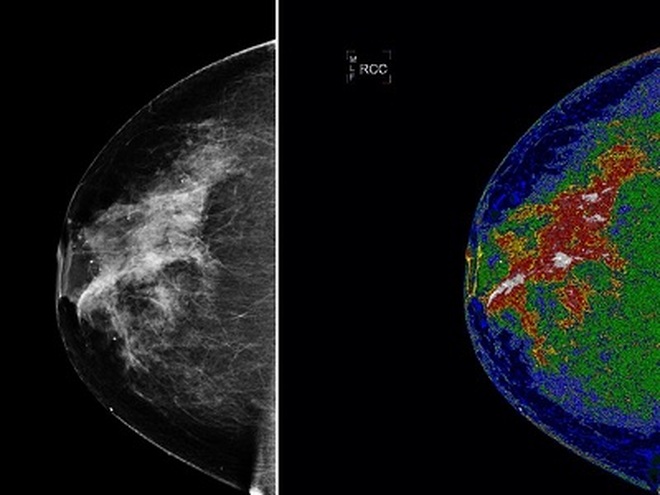

Có những dấu hiệu này coi chừng ung thư vú quay trở lại

(Dân trí) - Ung thư vú có tái phát tại cùng vị trí với khối u ban đầu hoặc lan ra vùng bên cạnh, thậm chí di căn ca đến phổi, gan và xương.